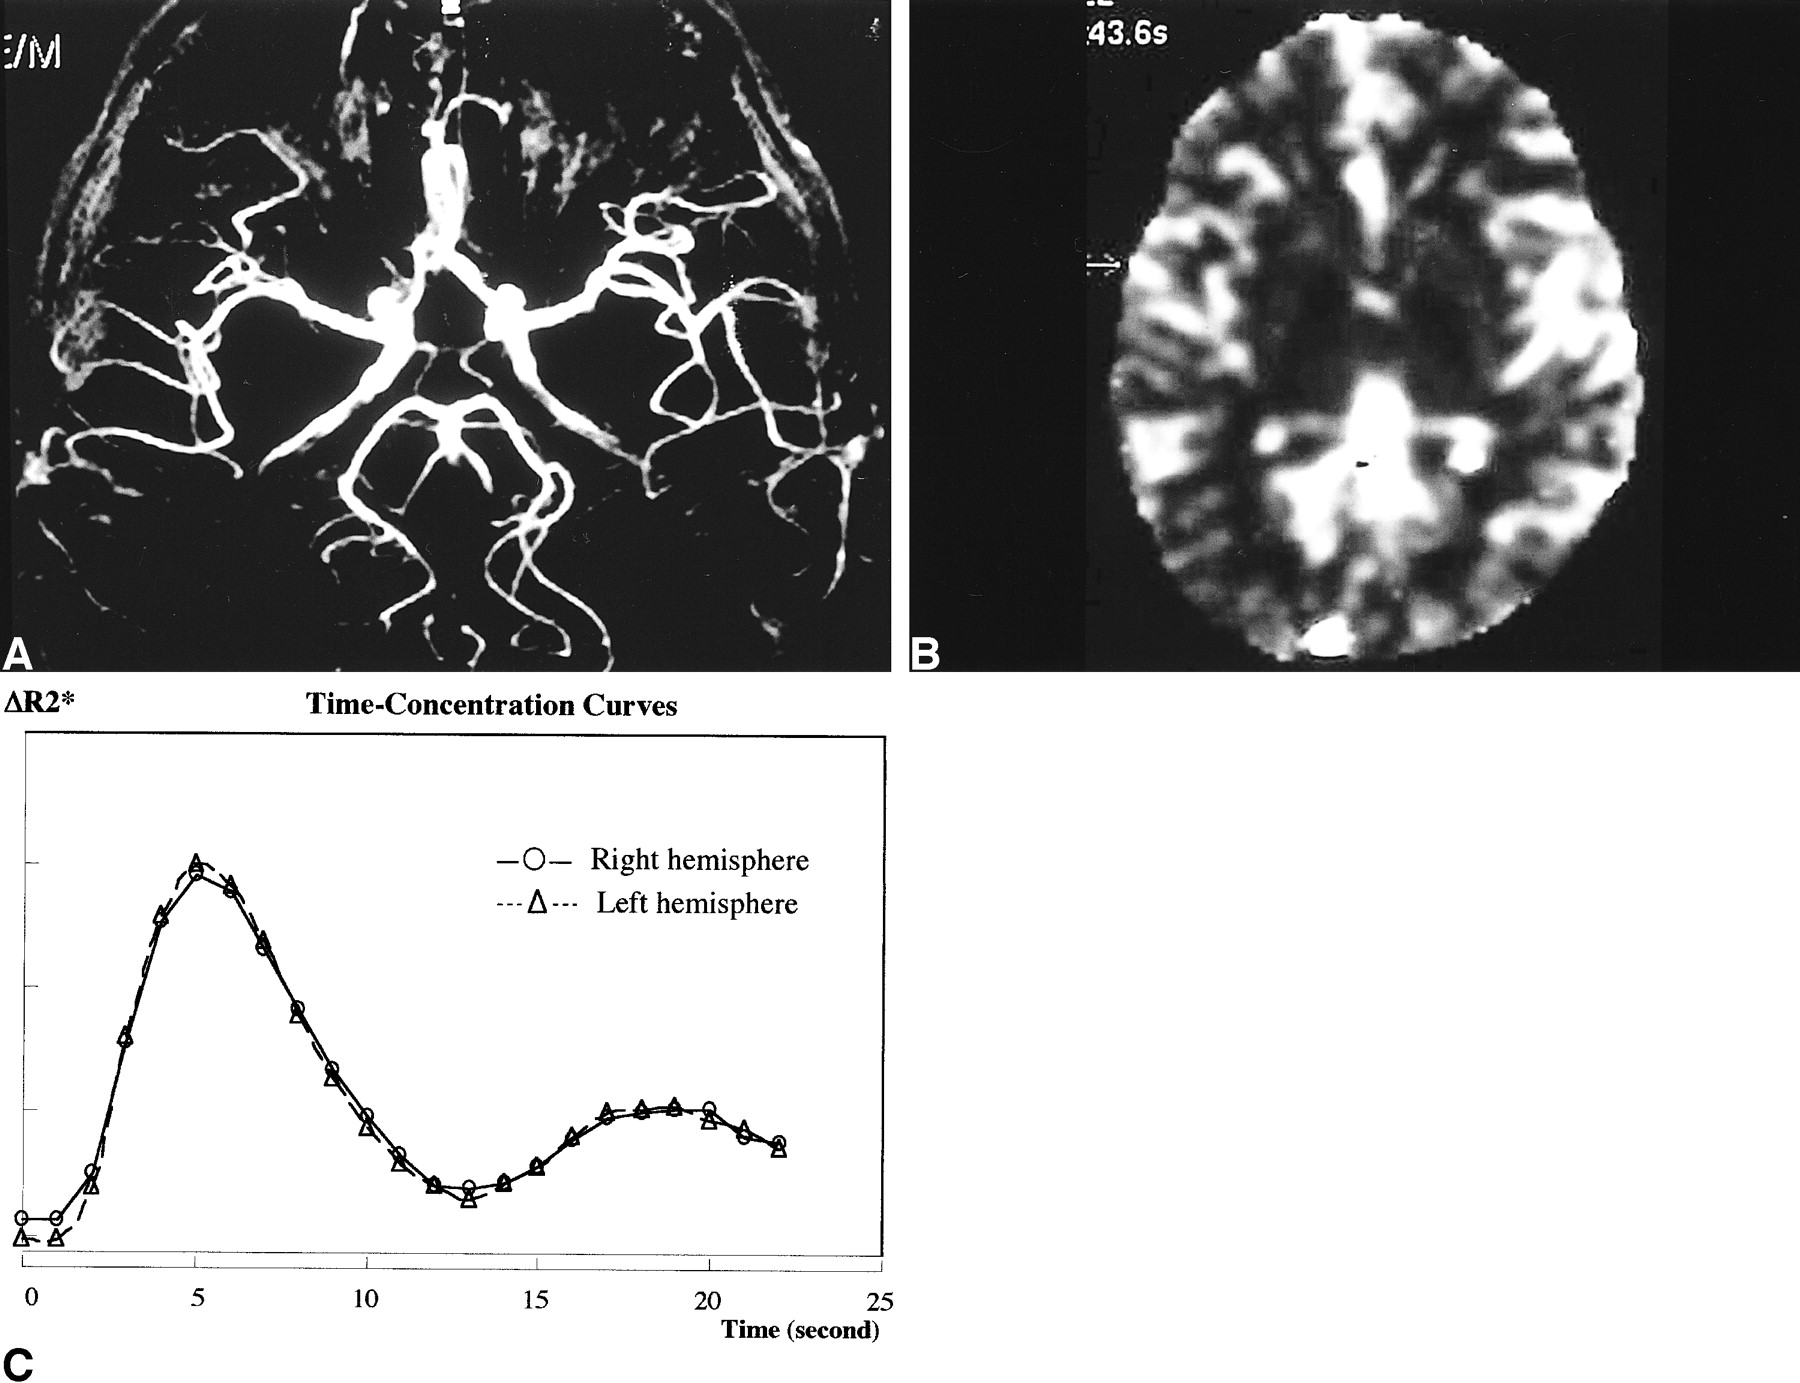

Repeat MRA and perfusion MR imaging 1 month after the attack.

A, MRA shows a symmetric appearance of the middle and posterior cerebral artery branches.

B and C, rCBV map (B) with time-concentration curves (C) also shows symmetric perfusion of both cerebral hemispheres.

MR imaging was performed when she had recovered from left-sided hemiplegia but still felt a right-sided headache 47 hours after onset and 39 hours after the resolution of left-sided hemiplegia. Routine T1-weighted images, T2-weighted images, and fluid-attenuated inversion recovery images showed no abnormalities. MR angiography (MRA) was also performed with a 3D time-of-flight sequence. This image showed dilatation of both the middle and posterior cerebral artery branches on the right side (Fig 1A). In addition, perfusion MR imaging with field echo type echo-planar imaging was performed. This image showed hyperperfusion of the right cerebral hemisphere compared with the left cerebral hemisphere (Fig 1B and C). One month later, when her symptoms were completely resolved, repeat MRA and perfusion MR imaging were performed. These images showed a symmetric appearance of the middle and posterior cerebral arteries, as well as symmetric perfusion of both cerebral hemispheres (Fig 2 A–C).